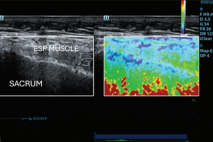

POCUS NEL CONTESTO PREOPERATORIO – CUORE Fabio Magarotto1, Federica Arturi1, Gabriele Melegari2 Università degli Studi di Modena e Reggio Emilia, Scuola di Specializzazione Anestesia e Rianimazione, Terapia Intensiva e del…